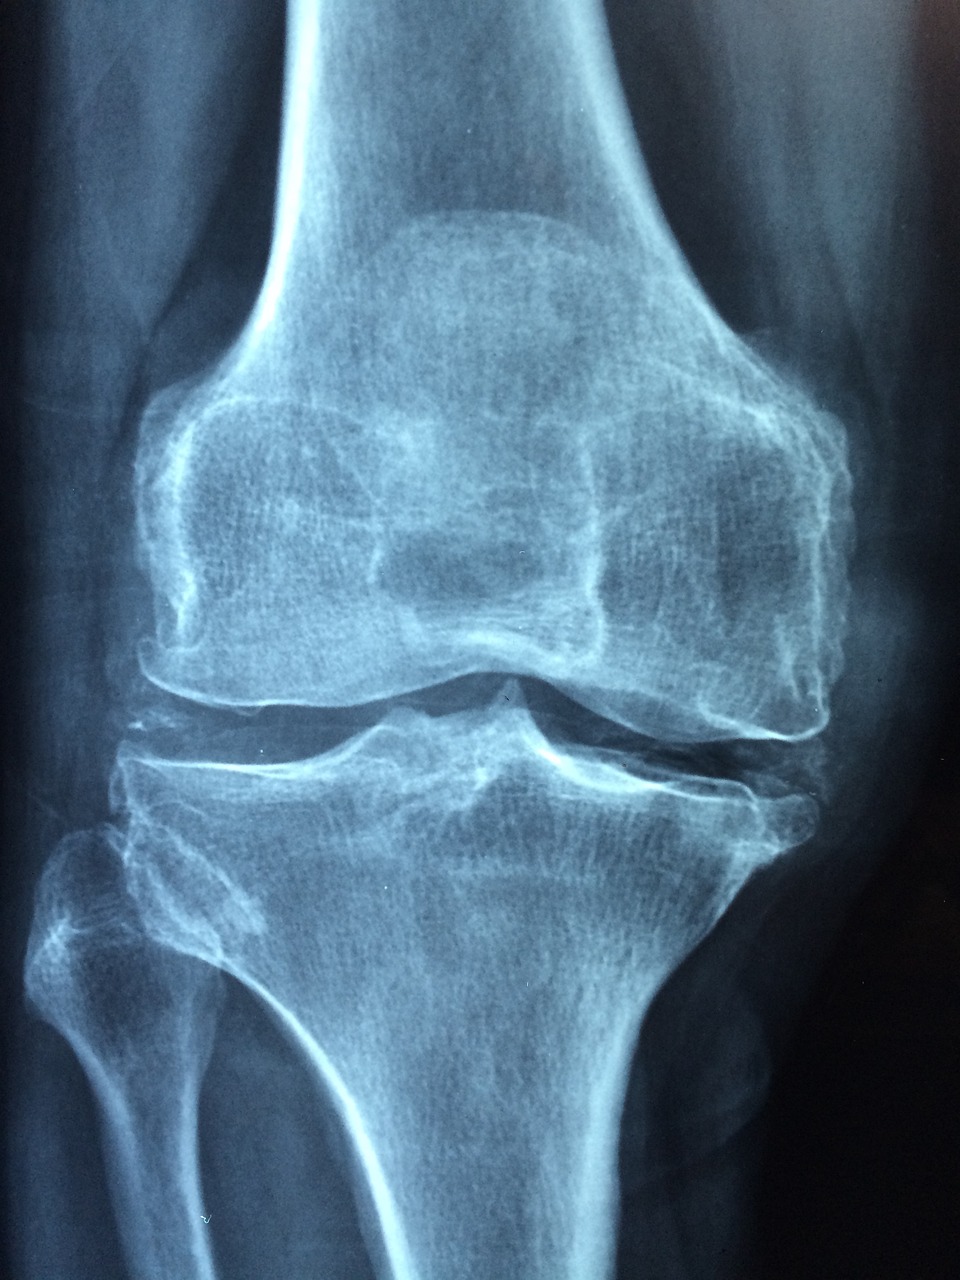

1. 연골 보호 & 관절 건강 개선

✔ 콘드로이친은 연골의 수분을 유지하고 탄력을 높여 관절을 보호하는 역할을 합니다.

✔ 퇴행성 관절염(골관절염) 환자의 통증을 완화하는 효과가 있습니다.

✔ 무릎 관절뿐만 아니라 손목, 어깨, 허리 관절 건강에도 도움을 줍니다.

2016년 유럽 류마티스학회(EULAR) 연구에서는 콘드로이친이 퇴행성 관절염(골관절염) 환자의 통증을 유의미하게 줄이는 효과가 있다는 결과를 발표했습니다.

- 콘드로이친 1200mg을 6개월간 복용한 그룹에서 무릎 관절 통증이 평균 20% 감소

- 관절 강직이 개선되었으며, 장기 복용 시 연골 손상이 늦어지는 경향 확인